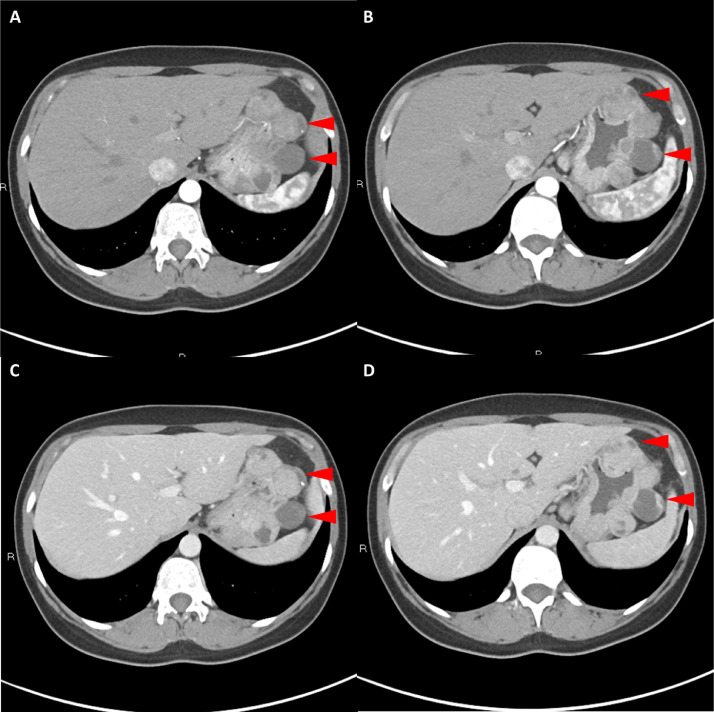

胸部、腹部和骨盆的對比增強動脈和靜脈期 CT 顯示多個圓形、主要是血管豐富的異質腫塊,具有囊性和實性成分,起源于胃底和胃體(圖 2-4)。 病變部分呈外生結構,被認為位于粘膜下層。 在頸部多發(fā)同步性副神經節(jié)瘤的情況下,賊初的鑒別診斷包括多發(fā)性副神經節(jié)瘤、多發(fā)性 GIST 以及轉移性疾病。

Fig. 3

圖 3:多個胃腸道間質瘤的冠狀和矢狀圖像。 (A 和 B)冠狀動脈相對比增強 CT 圖像顯示胃賁門產生的外生性腫塊。 (C 和 D)矢狀動脈相位對比增強圖像顯示腫塊的異質性和外生結構。